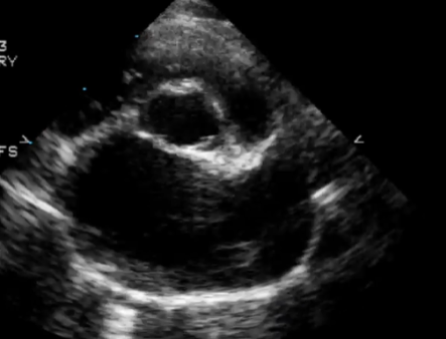

Giãn nhĩ MC 4 buồng cạnh ức phải

Giãn nhĩ mặt cắt Mercedes và 4 buồng cạnh ức phải